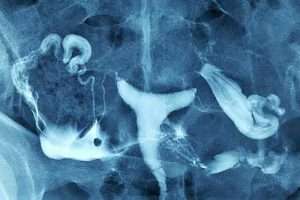

Uterus Didelphys

Komplet Septalı Uterus